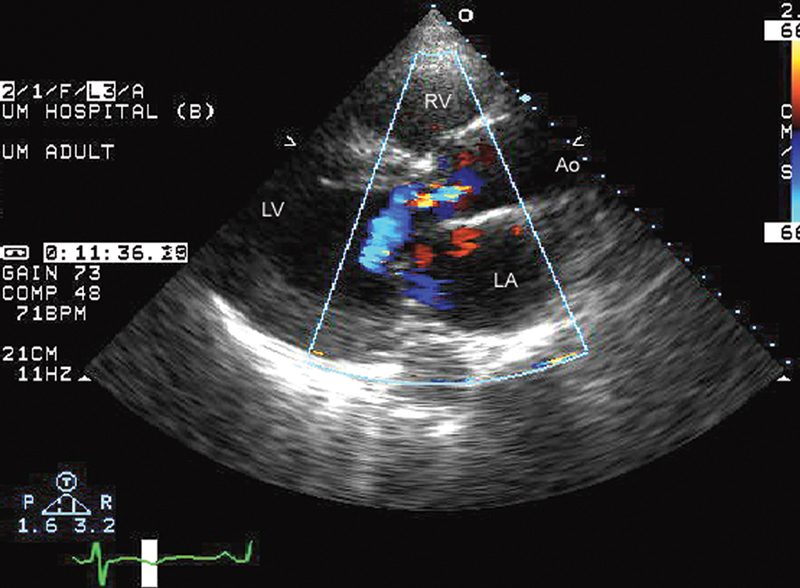

فحوصات تشخيصية لبعض امراض القلب والشرايين التاجية